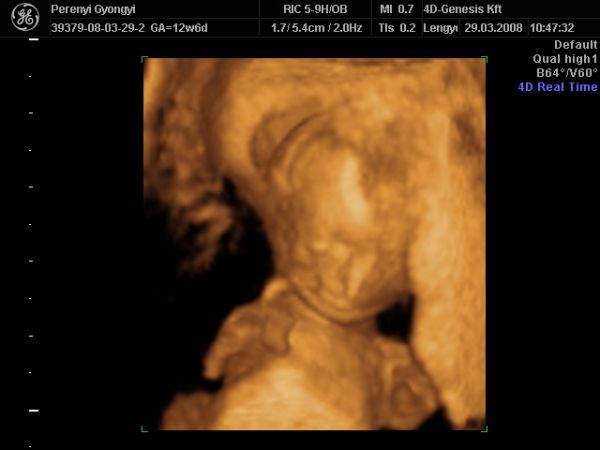

NHS-ben (TB kb), ami ingyen van 2db Uh van...12 és 20 hetesen. Ezen kívül minden hónapban találka a midwife-al, aki vizeletet néz, vérnyomást mér, megkérdezi hogy vagy, és elbeszélget veled, ha kérdésed, problémád, félelmed van. Aztán vannak a magán kórházak, ahova a középosztály felettiek járnak. Itt ugye annyit mehetsz, amennyit bír a pénztárcád, de mivel itt az előbbi a bevett szokás, sok nő nem kér semmi extrát. A privát ellátásért és szülésért viszont a végén kb egy 500-600 fontos számlát kapsz. Akire vigyázok, ő is ennyiért született. De ők nem kértek semmi extrát, 4D-re sem mentek el. Ja és aki NHS-re jár, de nem bír magával, az elmehet UH studiokba, amik a 4D-re mennek rá, de van 2D-s korai Uh is...mint pl majd én is leszek nagy valószínűség szerint.